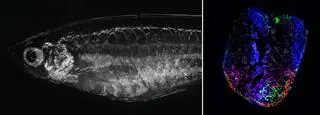

Z lewej: danio pręgowany pod mikroskopem. Z prawej: serce ryby 7 dni po uszkodzeniu. Czerwony kolor wskazuje aktywność naprawczą